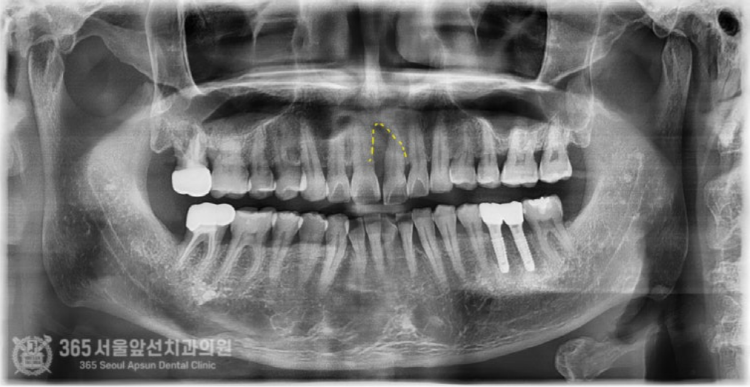

촬영일시 : 2024.07.02. 풍치로 인한 염증 부위를 색상으로 표시해보았습니다. (노란색) 3차원 CT를 이용하여 분석해보니 잇몸뼈가 염증으로 인해 녹은 상태로 매우 심각했습니다.....ㅠㅠ 촬영일시 : 2024.07.02. 결국 해당 치아는 발치를 하게 되었고, 임플란트 식립과 동시에 염증으로 인해 없어진 뼈를 재건하는 골이식을 시행하게 되었습니다. 발치를 하고 나서 임플란트 식립 및 골이식 수술 전 확인해보니 염증으로 소실된 뼈가 상당합니다. 촬영일시 : 2024.07.02. 임플란트를 식립했고 그 위로 두툼하게 골이식을 시행합니다. 일반적으로 골이식은 흡수되는 양이 상당합니다. 그래서 앞니 부위와 같이 미적으로 중요한 부위에서는 자연스러운 잇몸의 볼륨을 위해서 흡수되는 양을 감안하여 많은 양의 골이식을 시행하고있습니다. 임플란트를 식립 후에는 보통 작은 임시틀니를 드리고 그걸 사용하시는 경우가 많은데요. 지금처럼 골이식이 많이 들어간 경우에는 임시틀니를 사용할 경우 이식한 뼈가 제대로 성숙되지 못하는 경우가 많기에 다른 방식의 임시치아를 해드리고 있습니다. 위 환자분께서도 붙이는 형태의 임시치아를 해드렸고 잘사용하셨습니다. 촬영일시 : 2024.11.01. 4개월이 지나서 임플란트가 뼈와 잘 결합되었구요. 이식한 뼈도 단단해졌기에 슬슬 본 뜰 준비를 해봅니다. 동그랗게 회색 단추가 달려있는데요. 치유지대주라고 부르는 구조물로 이걸 이용하여 본을 뜨게 됩니다. 촬영일시 : 2024.11.05. 완성된 최종 보철물입니다. 사실 중간에 임플란트와 연결된 임시치아를 사용하여 잇몸 모양을 잡아주는 과정을 거쳤는데요. 아쉽게도 해당 과정에 대한 사진이 없군요 ㅠㅠ 이렇게 섬세하고 복잡한 과정을 거쳐서 임플란트 치료가 마무리 되었습니다 ㅎㅎ 이식된 뼈 부위도 통통하게 뼈가 잘되어있습니다 ㅎㅎ 만족스럽습니다. 촬영일시 : 2024.11.05. 치료가 마무리 된 후 엑스레이 사진입니다. 최종 보철물 장착 완료까지 자연스럽게 잘 마무리되어 기분이 좋네요. 직원분께서 가족의 치료를 믿고 맡겨주셨고, 그에 보답할 수 있어 기분 좋은 치료 증례였습니다. 앞으로도 더 유익한 치료 증례로 찾아뵙겠습니다. 도화역치과 365서울앞선치과의원이었습니다. 감사합니다. [ 치료기간: 2024년 7월2일 ~ 2024년 11월 5일 ] ※ 365서울앞선치과의원의 모든 포스팅은 각 진료과 의료진이 직접 작성합니다. 365서울앞선치과의원 블로그의 임상 케이스 게시물은 환자분께 의학적으로 정확하고 상세한 정보를 드리기 위해 각 진료과 의료진이 직접 작성하며, 모든 증례 사진은 본원 의료진이 직접 시술한 증례를 촬영한 것으로, 의료법 제23조, 제56조에 의거하며 환자분의 동의를 얻어 포스팅에 사용하였습니다. 또한 해당 케이스는 본 환자분의 치료 결과이며, 환자 상태에 따라 치료의 결과는 달라질 수 있습니다. |